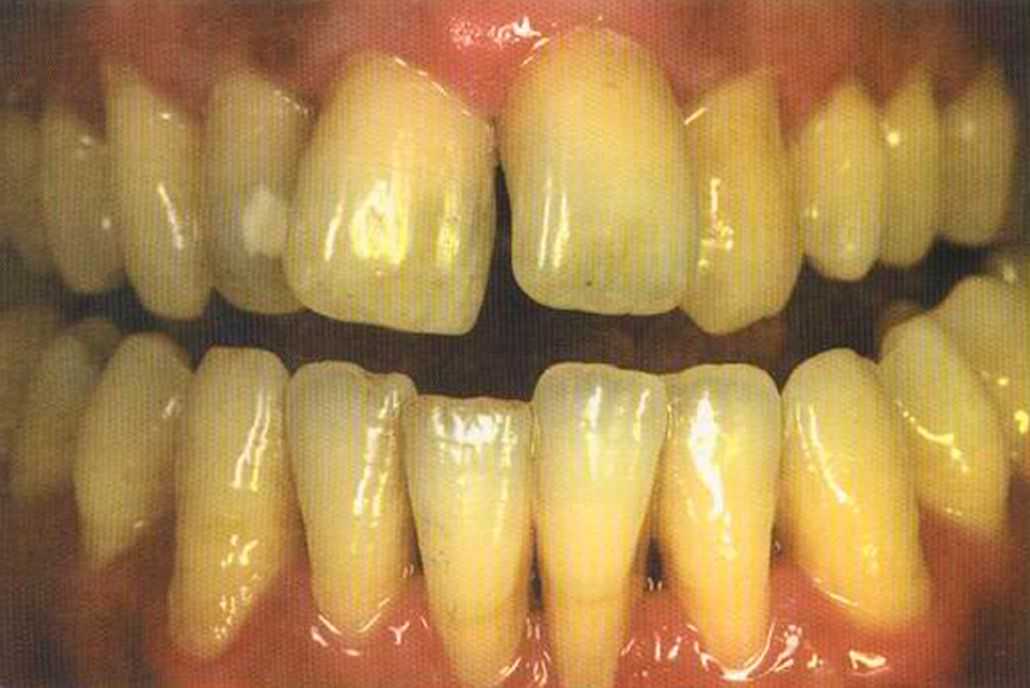

Эта женщина пришла в клинику доктора Лангханке с металлокерамической реставрацией.

Ей не нравились типичные в таких случаях темные края коронок и опаковость керамики.

Отмечаем, что десна здоровая. Она гармонирует с коронкой ln-Сегат за счет отличных свойств материала

и отличного краевого прилегания.

Теперь коронки в области боковой группы зубов не нравятся, и в скором времени их тоже будем переделывать.

Коронки выполнялись в моей лаборатории вместе с пациентом. Мы работали долгих четыре часа, чтобы всем понравился результат. Обратите внимание на отражение света по краевым валикам. Мезиальные валики коронки 12 зуба гармонично переходят в дистальные валики 42 зуба. В идеальном варианте «отражающиеся валики» должны проходить по прямой линии. Это привило для всех мезиальных и дистальных валиков фронтальной группы зубов. Оно имеет очень важное значение и влияет на результат нашей работы.

Эти валики проходят перемещаясь, однако по одной линии. Примером здесь являются мезиальные поверхности на коронке 11 и на 31.